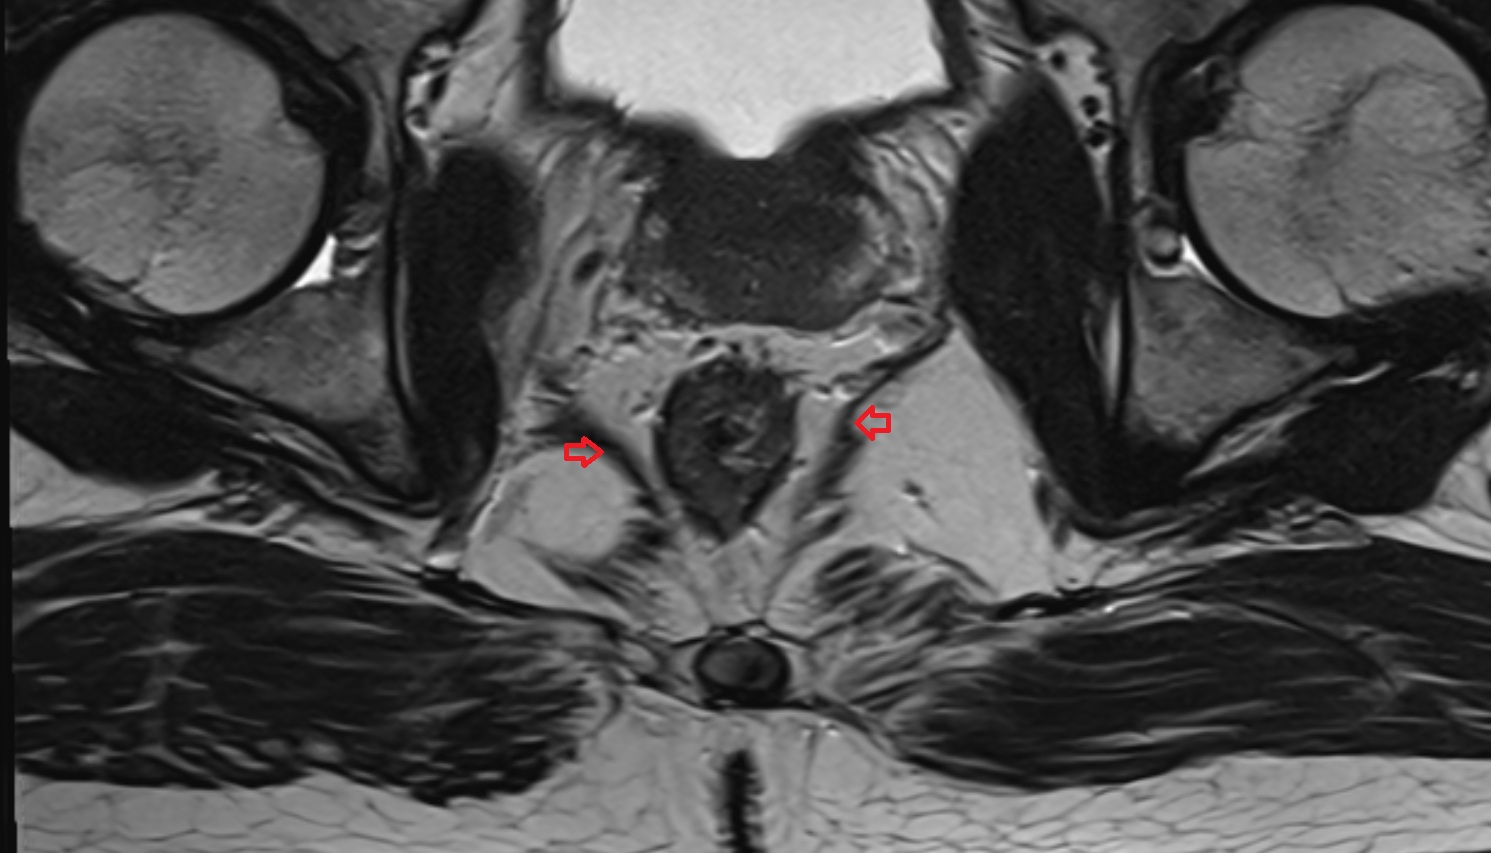

- Peripheral zone of prostate

- Anterior Fibromuscular Stroma of prostate

- Central zone of prostate

- Transitional zone of prostate